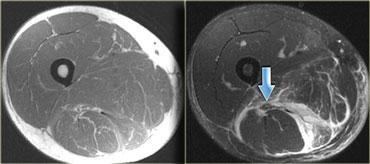

Bên trái là hình ảnh bệnh nhân bị tổn thương cơ bụng chân độ 2.

Có tổn thương độ thấp ở đầu ngoài.

Bên trái là cùng một bệnh nhân.

Cũng có tổn thương mức độ trung bình ở đầu trong.

Lưu ý các ổ tích tụ dịch xung quanh đầu cơ.

Dịch càng nhiều, mức độ tổn thương càng cao.

Bên trái là cơ thẳng đùi bị tổn thương.

Các hình ảnh cho thấy tổn thương mức độ vừa, với sự biến dạng cấu trúc và một ổ tụ dịch (mũi tên).

Lưu ý phù nề tại chỗ nối cơ-gân dạng hai lông chim.